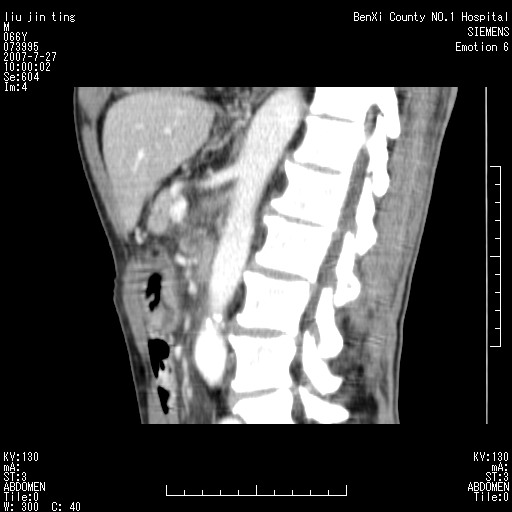

腹痛,背痛,无恶心呕吐,不黄,彩超示胰腺钩癌,ct扫描病灶平扫30-40hu,增强后动脉期40--60hu,静脉期50-68hu,真的是钩突上的么?您要试一试么?

动脉期

静脉期

沿着肠系膜上动脉呈匍匐性生长的软组织肿块,形态不规则,包绕肠系膜上动脉,呈明显强化,考虑来源于肠系膜的恶性肿瘤

沿着肠系膜上动脉呈匍匐性生长的软组织肿块,形态不规则,包绕肠系膜上动脉,呈轻-中度强化,考虑来源于肠系膜的恶性肿瘤。

钩突是正常的,只见腹膜后淋巴结的肿大,考虑淋巴瘤或转移可能。